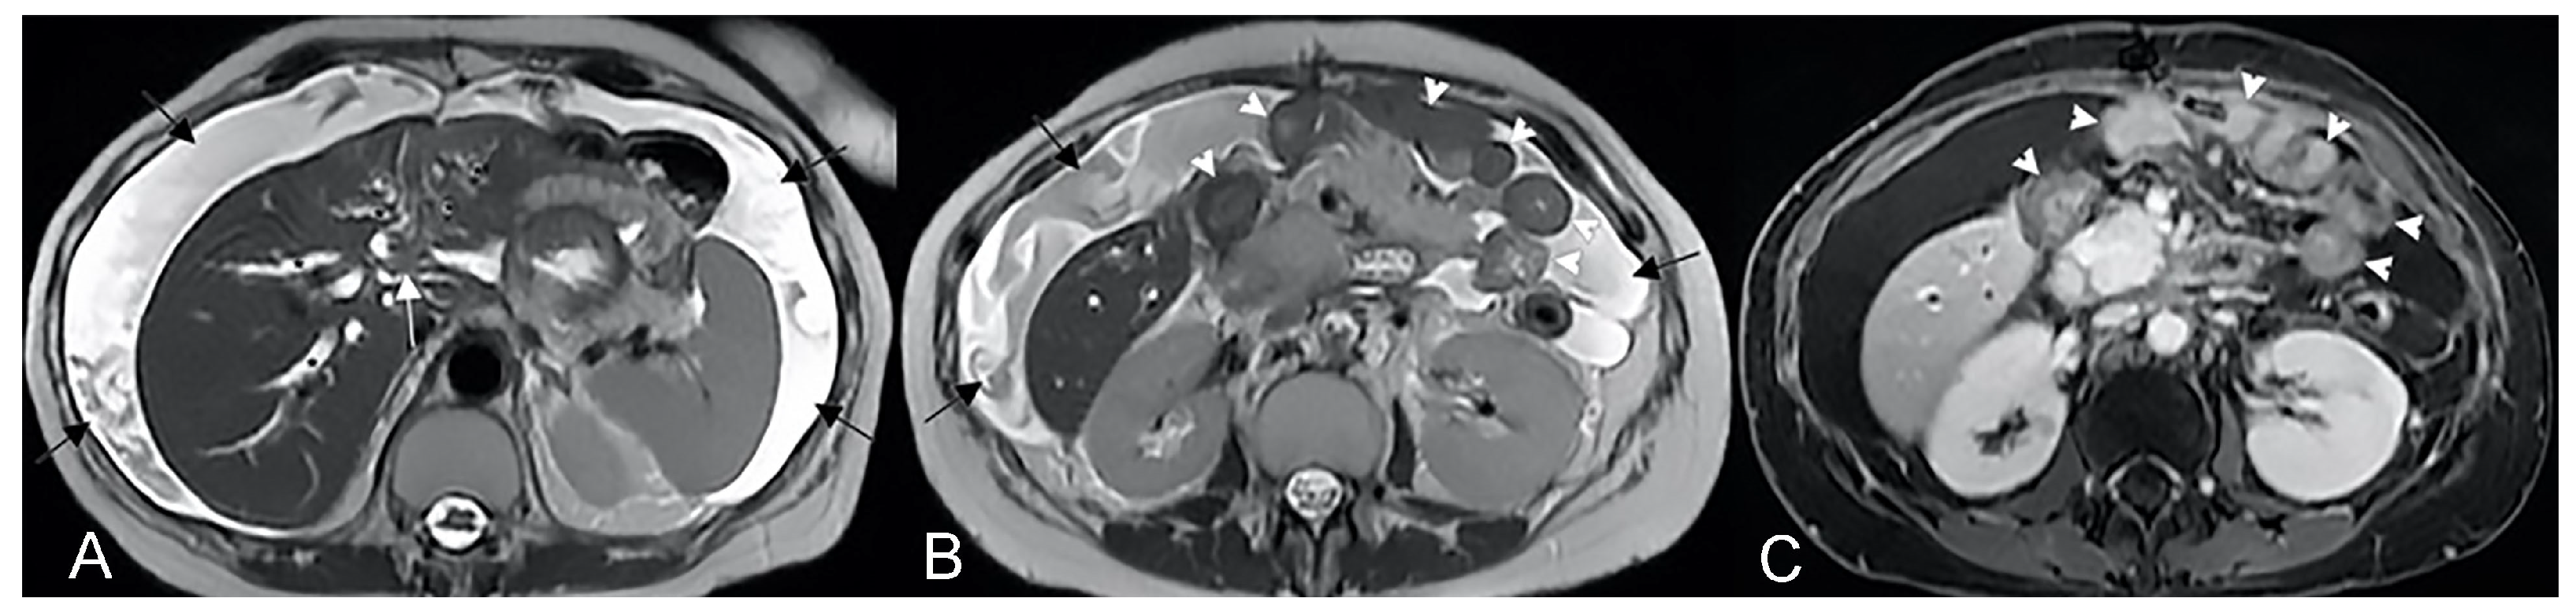

Figure 16.

Degree of wall thickening and type of involvement along bowel circumference. (A) Axial T2-weighted image shows mild thickening (<1 cm) of an ileal loop in the pelvis (arrow). (B) Axial T2-weighted image shows moderate symmetric thickening (>1 cm and <2 cm) of a small bowel loop (black arrow), supported by edema of the submucosal layer. (C) Axial T2-weighted image shows marked asymmetric thickening (>2 cm) of an ileal loop in the pelvis (arrows); the other side of the bowel wall is less thick (arrowheads).

Thickening throughout the intestinal loop circumference might be eccentric (asymmetric) or circumferential (symmetric) depending on the type of involvement (Figure 16B,C) [29,30]. According to the length of the pathological bowel tract, thickening can be focal, segmental, or diffuse. Bowel thickening is defined as focal when the pathological tract is shorter than 5 cm in length (Figure 17A); segmental thickening refers to 6–40 cm in length of thickened small bowel (Figure 17B), while it is considered diffuse when a large amount of small bowel loops (>40 cm) is affected (Figure 17C) [29,30]. After contrast-medium injection, various patterns of wall enhancement can be described: stratified, white, and gray [30]. Contrast enhancement is classified as stratified when there is hyperintensity of the inner layer (muco-sa), hypointensity of the intermediate layer (submucosa), and hyperintensity of the outer layer (muscle and serosa layers); this is caused by mucosal hyperemia and submucosal edema. If stratified contrast enhancement is associated to fat deposits in the submucosal layer, it is called “fatty halo” sign [30,31].

Figure 17.

Focal, segmental, or diffuse thickening. (A) Axial T1-weighted after gadolinium injection image shows focal thickening of the distal ileum, shorter than 5 cm in length (arrow), with avid contrast enhancement. (B) Coronal T1-weighted after gadolinium injection image shows segmental thickening of an ileal loop in the pelvis, with 6–40 cm in length (arrow). (C) Axial T1-weighted after gadolinium injection image shows diffuse thickening of a large amount of small bowel loops (>40 cm) (arrows).

Once bowel pathology has been identified, the radiologist’s first step is trying to define the benign or malignant nature of the alteration. When intestinal pathology is found, the radiologist’s initial step is to determine if the alteration is benign or malignant, starting from patient’s history and clinical information. In the presence of small bowel thickening, a benign condition is probable when thickening is mild or moderate in degree, focal or segmental and symmetrical (Figure 17A,B), with homogeneous or stratified contrast enhancement; on the other hand, a malignancy is probable when there is a significant mural thickening, focal and asymmetrical, with inhomogeneous contrast enhancement (Figure 18) [29].

Figure 18.

Example of marked thickening due to a malignant condition. (A) Axial T2-weighted and (B) axial T1-weighted after gadolinium injection images show a marked, focal, and asymmetrical small bowel thickening, with inhomogeneous contrast enhancement (arrowheads), caused by a malignant condition.

Diffuse thickening, especially when almost all small bowel loops are affected (Figure 17C), is always due to benign diseases such as infections, inflammation, and parietal edema, as observed in hypoproteinemia or mesenteric ischemia. Sometimes, marked thickening can be also noticed in benign diseases, such as severe infections (Figure 19) [29].

Figure 19.

Example of marked thickening due to a benign condition. Axial T2-weighted image shows marked segmental thickening of a small bowel loop in the right abdominal quadrant (arrows), due to a benign condition (Crohn’s disease).